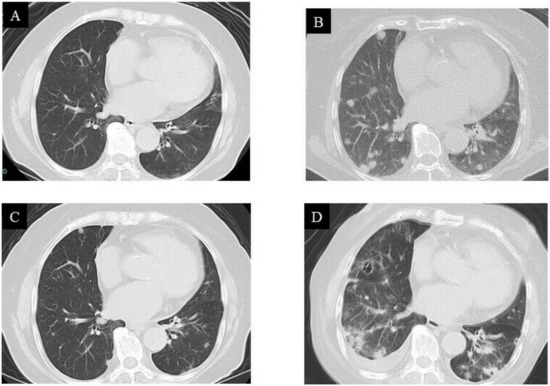

2. Case Presentation